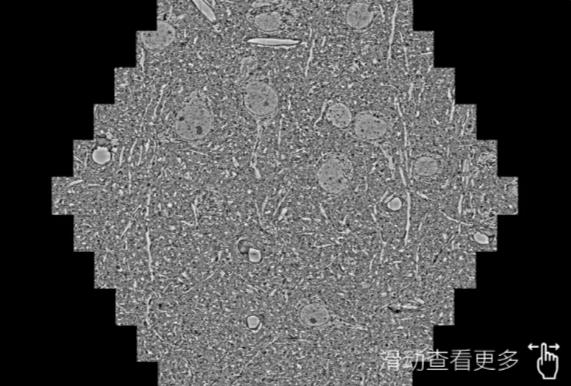

鼠脑切片。左图使用盘锦蔡司盘锦扫描电镜MultiSEM706对165μmx143pm面积区域成像,耗时仅需1.5秒。右图为鼠脑切片中30μm区域放大效果。样品由芝加哥大学B.Kasthuri提供。

使用蔡司高速盘锦扫描电镜MultiSEM对1mm²人脑皮层组织进行高分辨成像,并对其中的各种细胞结构进行三维重构分析。左图展示了2x3mm²组织平面中锥体神经元的三维重构效果。右图显示了局部体积神经元三维重构。图像由哈佛大学chtman实验室提供,渲染图由D. Berger 制作。